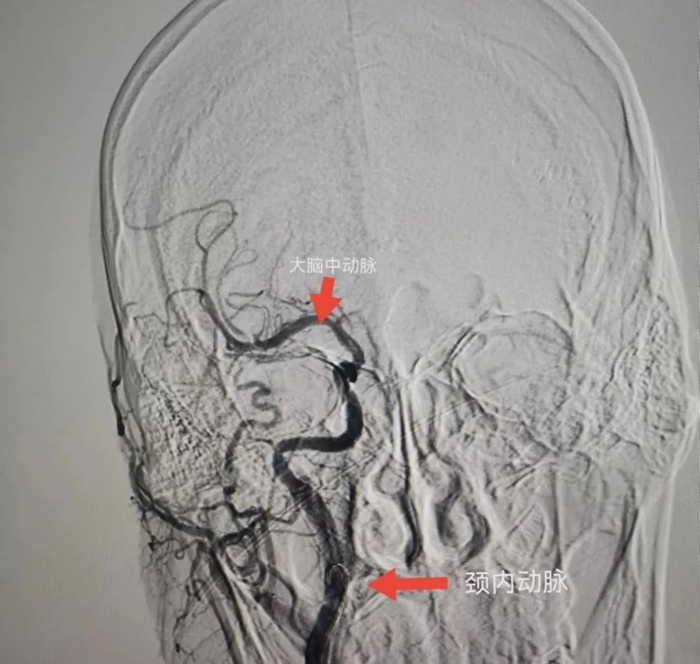

與患者女兒溝通,征得患者女兒同意后,立刻聯(lián)系CT室,半小時內(nèi)完成CT檢查,證實患者右側(cè)頸內(nèi)動脈和右側(cè)大腦中動脈閉塞,存在70毫升的缺血腦組織,有取栓適應癥。再次和患者女兒溝通,患者女兒接受風險簽字手術(shù)。立刻聯(lián)系介入室和麻醉科,一個半小時完成手術(shù)。

術(shù)中給予患者右側(cè)頸內(nèi)動脈植入支架和右側(cè)大腦中動脈取栓,患者血管達到3級再通。術(shù)后第二天,患者神志轉(zhuǎn)清醒,左下肢可抬起。術(shù)后第5天,患者左側(cè)肢體均可活動達到4級肌力,左手可持物,能獨立行走。

患者腦CTA結(jié)果

血管內(nèi)治療后的結(jié)果